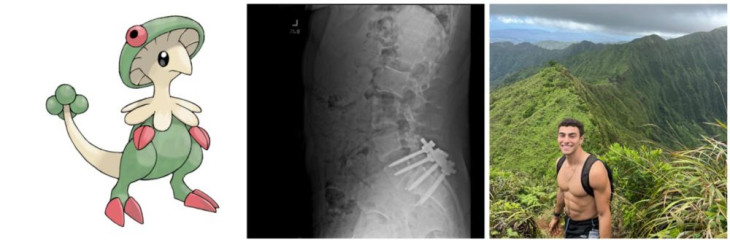

A 26 éves Luigi Mangione semmiképp sem nevezhető átlagos merénylőnek: gazdag családból származik, elitegyetemet végzett, ismerősei rendkívül okosnak és közkedveltnek írták le, alapvetően jóképű fiatal férfi, aki előtt úgy tűnt, fényes jövő áll. Hogy pontosan miért támadt, azt hosszú hónapokig vizsgálják majd. Ami azonban jelenleg biztosnak látszik, az az, hogy egy szörfbaleset után jelentkező hátfájdalmai miatt életminősége jelentősen megromlott. Másfél évnyi kezelés után hátműtéten esett át, ezután pedig haragja az amerikai egészségügyi rendszer ellen fordult. Végül hónapokra eltűnt családja és ismerősei elől, olyannyira, hogy édesanyja eltűnt személyként is bejelentette.

Fotó: X/Luigi Mangione